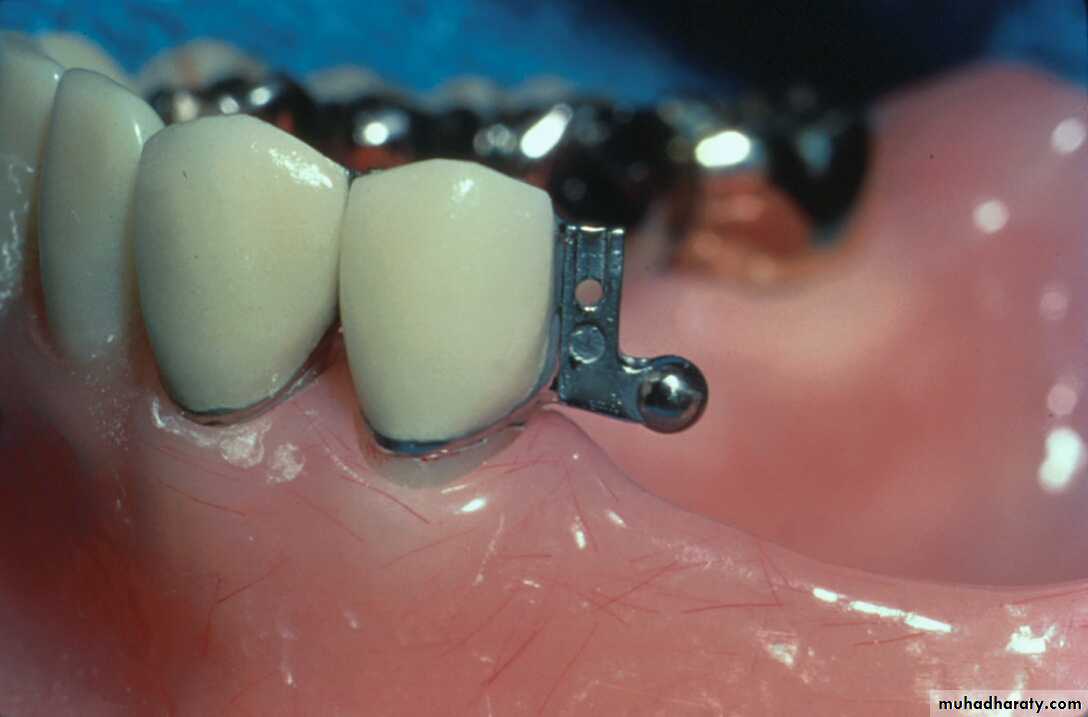

Extracoronal Attachments

• Positioned entirely outside the crown contour ; therefore, the normal tooth contour is maintained & the possibility of devitalizing a tooth is reduced in comparison to the intracoronal variety.

- Resilient variety is usually indicated in distal extension RPDs.ERA Extracoronal Resilient Semiprecision Attachment